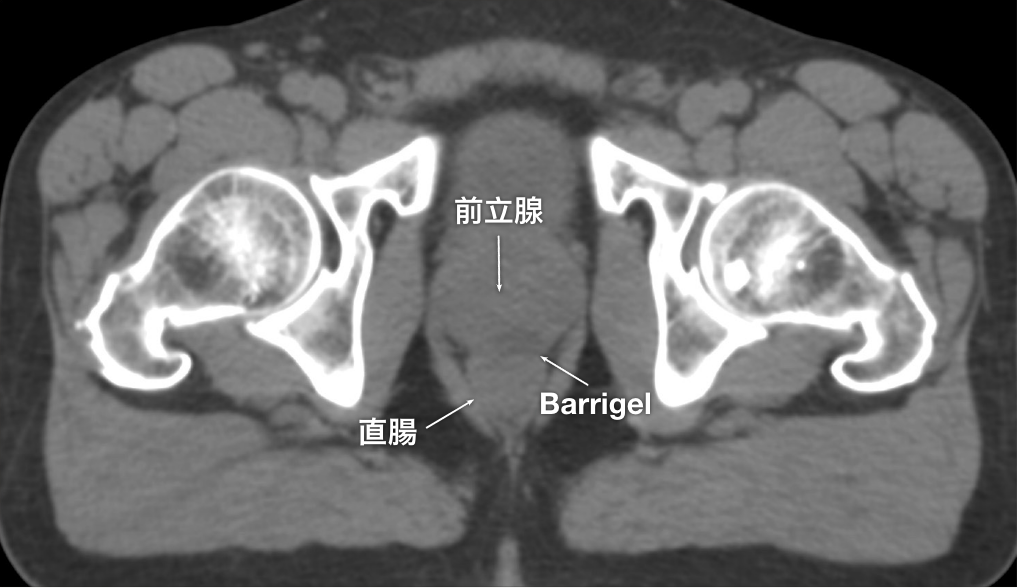

CT画像

CT画像提供:Suraj Singh, MD

Radiation Oncologist, Colorado, United States